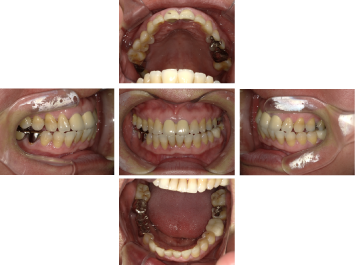

50代 女性 インプラント治療(GBR・ソケットリフト)

| 年代・性別 | 50代・女性 |

| 主訴 | Brの歯が取れそうなため、インプラントに変えたい。 |

| 部位 | 左下567 左上④5⑥ 右上67 |

| 治療期間 | 約3年9ヶ月 |

| 費用 | ¥3,224,500(税込) |